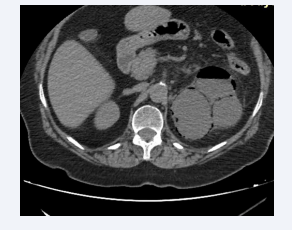

Axial section of an abdominal CT scan after intravenous  contrast injection at portal time showing an enlarged left kidney  with a nephrographic defect and surrounded by a posterior perirenal  collection containing air bubbles. The appearance is compatible with  class 3A EPN according to Huang et al.

Figure 1: Axial section of an abdominal CT scan after intravenous contrast injection at portal time showing an enlarged left kidney with a nephrographic defect and surrounded by a posterior perirenal collection containing air bubbles. The appearance is compatible with class 3A EPN according to Huang et al.